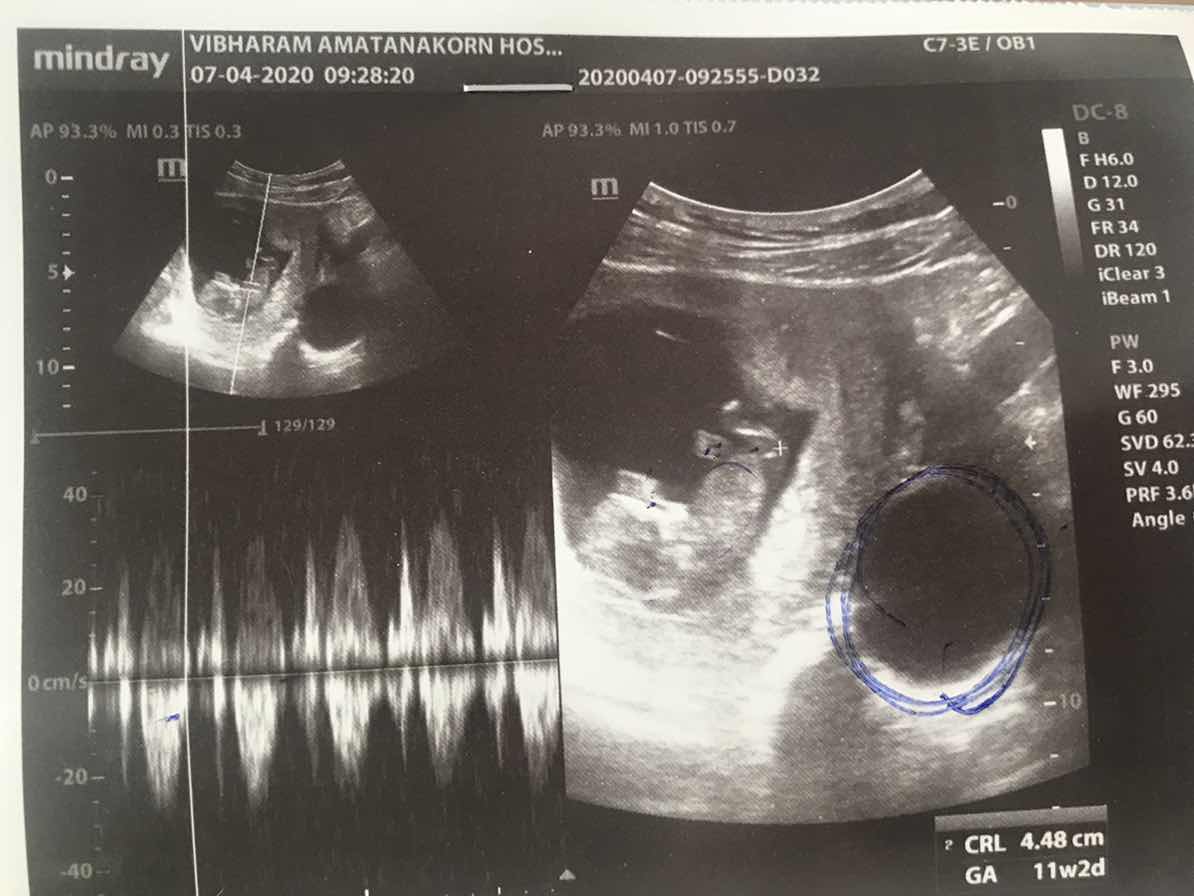

ปัจจุบันอายุครรภ์ 12 วีค 3 วัน แล้วแต่เมื่อช่วงอายุครรภ์ 11 วีค 5 วันหมอแจ้งว่าไม่เจอหัวใจน้องอยากขอดูใบซาวด์แม่ ๆ หน่อยได้ไหมคะ เป็นอย่างไรกันบ้าง

ตอน 11 วีคค่ะ

ตอน 10w+1d คะ

10+1 วีคค่ะ